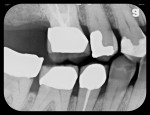

In another case, a 56-year-old man presented with severe bilateral mandibular tori (Figure 9) that made it impossible to take a radiograph using a rigid sensor that captured the entire tooth being evaluated. A flexible phosphor sensor, however, fit the patient’s anatomy with no difficulty or patient discomfort, and a radiograph was easily taken (Figure 10).